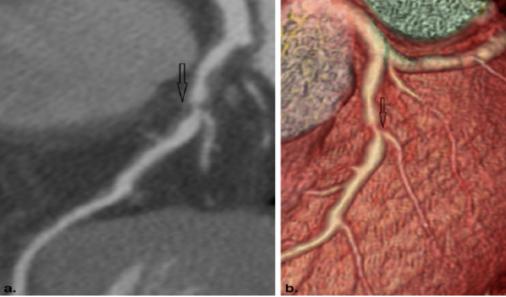

医生靠什么评估冠心病:1.心电图:大部分冠心病病人,没有症状发作时的心电图都是基本正常。所以,心电图正常不能排除冠心病。当出现心绞痛症状时,发生暂时的T波倒置,或ST段下移。心电图运动试验更加准确,通过运动增加心脏负担,在负荷的情况下观察会不会出现上述心肌缺血的心电图表现。2.影像学检查:包括心脏超声,冠状动脉CT血管成像,心脏核磁共振(MRI),核医学心肌灌注检查等。各种影像学检查各有优势,医生会根据您的病情选择合适的检查方法,目前应用比较广泛的是心脏超声和冠状动脉CT血管成像检查,特别是冠状动脉CT血管成像检查,可以直接观察到冠状动脉内是否存在斑块及血管狭窄,提供诊断冠心病的直接证据。当然,目前诊断冠心病的金标准还是经导管的冠状动脉造影检查,该检查属于有创检查,必须住院在医院导管室内完成,存在一定的风险性。可喜的是,上述冠状动脉CT血管成像等无创的影像学检查可以在门诊完成,且可以明确是否存在冠心病。故当您怀疑到自己存在冠心病时,一定不要讳疾忌医,及时就诊,让医生判断病情,早诊早治,以免延误病情。

冠状动脉CT血管成像示冠状动脉斑块形成,导致冠状动脉管腔狭窄,明确诊断冠心病